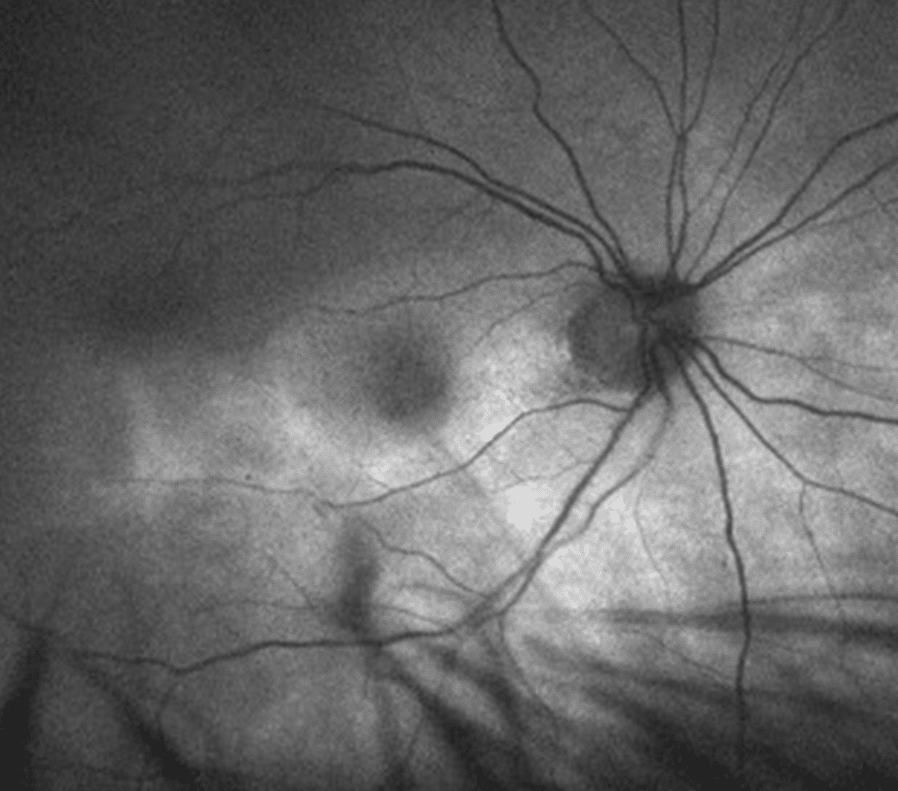

Retinitis periférica

Esta lesión suele presentarse de forma bilateral, típicamente en sectores temporales o nasales, en forma de triángulo blanquecino. Sobre esta lesión, que algunos autores describen como en «cristal esmerilado» aparecen lesiones puntiformes blanquecinas que afectan a capas más superficiales de la retina.